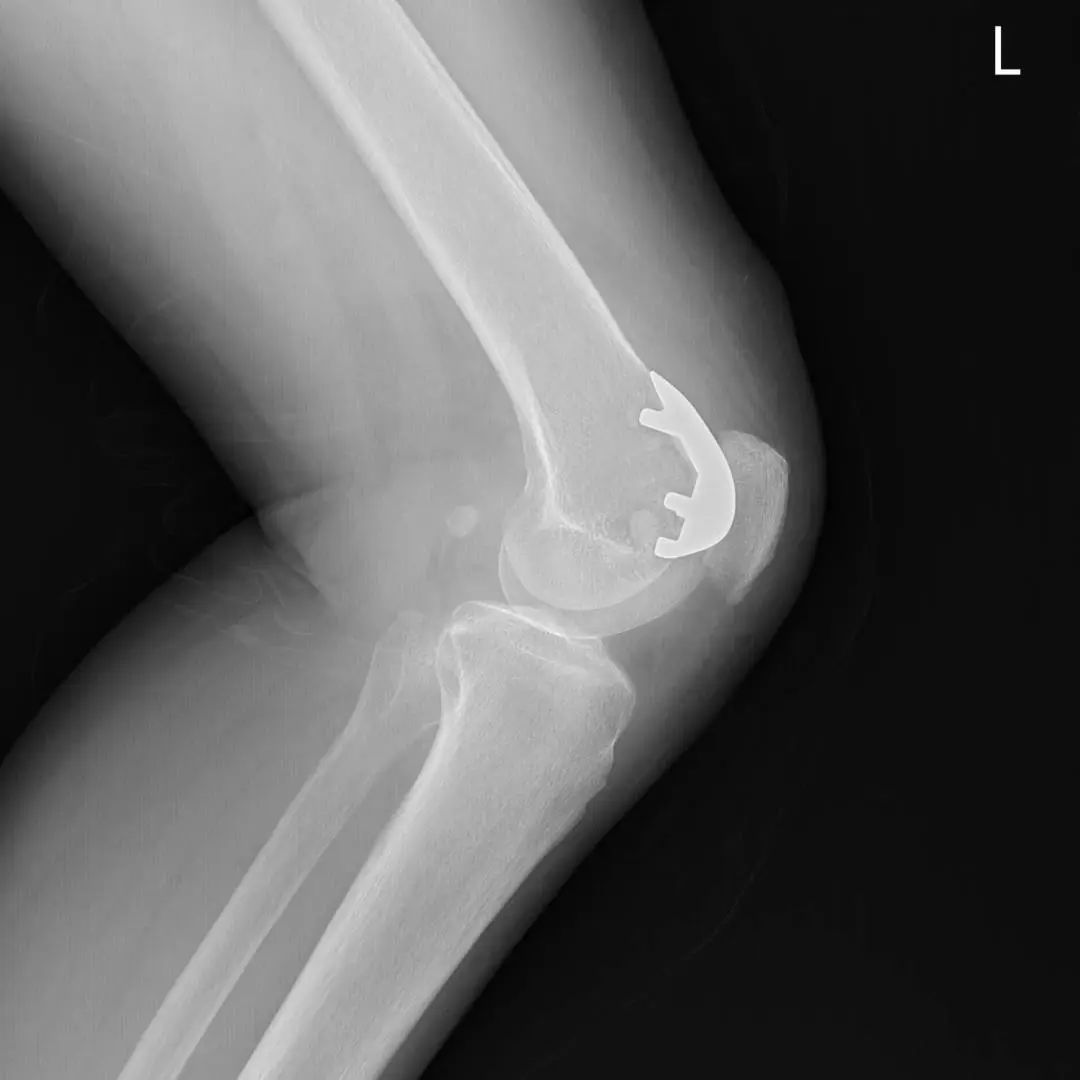

74岁的吕阿姨膝关节疼痛10余年,屈伸活动受限,外院就诊止痛药等保守治疗效果欠佳,拍片提示膝退行性骨关节炎。近日,她慕名来到上海市同济医院骨关节外科中心程飚主任门诊,程飚主任结合患者症状,影像学结果,体格检查,发现吕阿姨主要问题集中在膝关节内侧及髌股关节,膝关节外侧尚可。

为尽可能保留吕阿姨关节,程飚主任对定对吕阿姨进行膝关节部分置换手术,包括膝关节内侧单髁置换,髌股关节表面置换,尽可能减少膝关节截骨量,尽快恢复膝关节功能。吕阿姨术后第一天就开始下地走路了,她表示膝关节疼痛明显缓解,膝关节的活动范围也明显增加了,对程主任精准的手术治疗表示衷心的感谢。

部分膝关节置换手术目前已是非常成熟的治疗方法,亦属于保膝治疗的一种。主要包括单髁置换,髌股关节置换。单髁置换主要把膝关节内侧髁或者外侧髁表面已经磨损的部分替换成金属的假体和高分子聚乙烯耐磨垫片。髌股关节置换主要把髌股关节表面已经磨损的部分替换成金属的假体。

主要为退行性骨关节炎的患者,病变局限于内侧或者外侧胫股关节,可行单髁置换;

同时有髌股关节及单侧髁的病变,可行单髁+髌股关节表面置换。